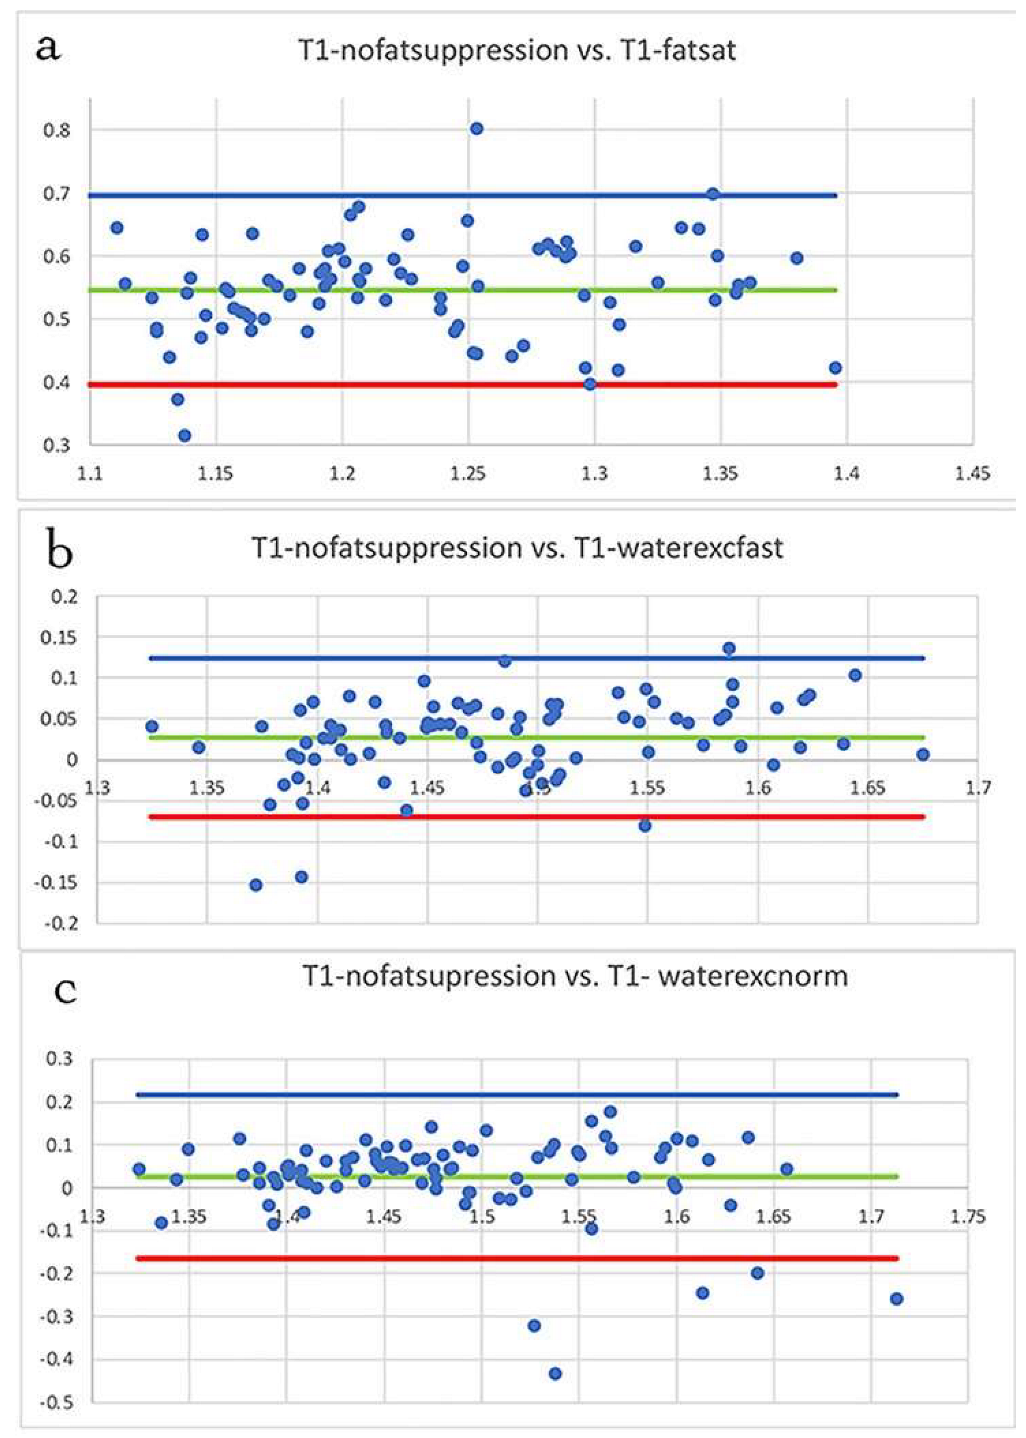

3.1. Fat Suppression

3.2. T1 Mapping